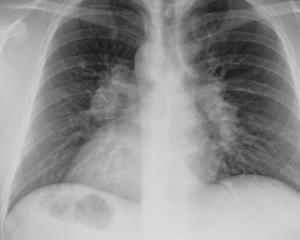

| Диагностика | Рентгенография грудной клетки (выявление характерных изменений), компьютерная томография высокого разрешения (КТ), бронхоскопия с биопсией, анализ крови (выявление повышенного уровня ангиотензинпревращающего фермента (АПФ) и кальция). | Биопсия пораженной ткани является золотым стандартом диагностики. |

Пациентам, у которых есть подозрение на саркоидоз легких, рекомендуется пройти несколько диагностических процедур. В первую очередь это компьютерная томография (КТ) легких и магнитно-резонансная томография (МРТ). Эти исследования помогают выявить очаговую диссеминацию и увеличение лимфатических узлов. Также полезно провести бронхоскопию.

Случаи, когда саркоидоз легких протекает без каких-либо симптомов, не являются редкостью. Обычно в таких ситуациях заболевание выявляется во время профилактического рентгенологического обследования.

Прогноз при саркоидозе легких значительно улучшается, если заболевание было диагностировано на ранних стадиях. Поэтому важно не игнорировать профилактические рентгенологические обследования.